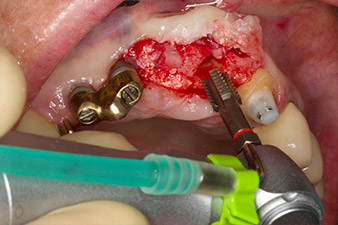

Following primary healing, the soft tissues were shaped using the basally lined bridge. Two months later the site was exposed by a slightly palatal alveolar ridge incision (Fig 2). The dimensions of the alveolar bone proved to be sufficient at position 22. Figures 2 and 4 show the preparation of the implant bed, the tapping and the implantation using Implantmed.

In order to compensate for the periodontal bone loss and achieve an aesthetically pleasing result, the implantation was combined with guided bone regeneration (GBR) with xenogenic replacement material and a collagen membrane

(Fig. 5 and 6).